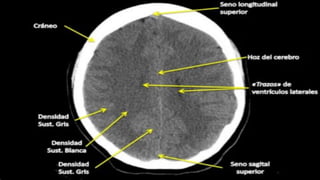

ESCALA DE GRISES CON LAS UNIDADES

Existe una escala de densidades tomográficas conocida como

la escala de Unidades Hounsfield (UH), la cual es básicamente

una escala de grises. En esta escala se asigna un valor

numérico a las densidades y va desde -1000UH (Muy negro =

aire), 0UH (Densidad de agua), y +1000UH (Muy blanco =

metal).